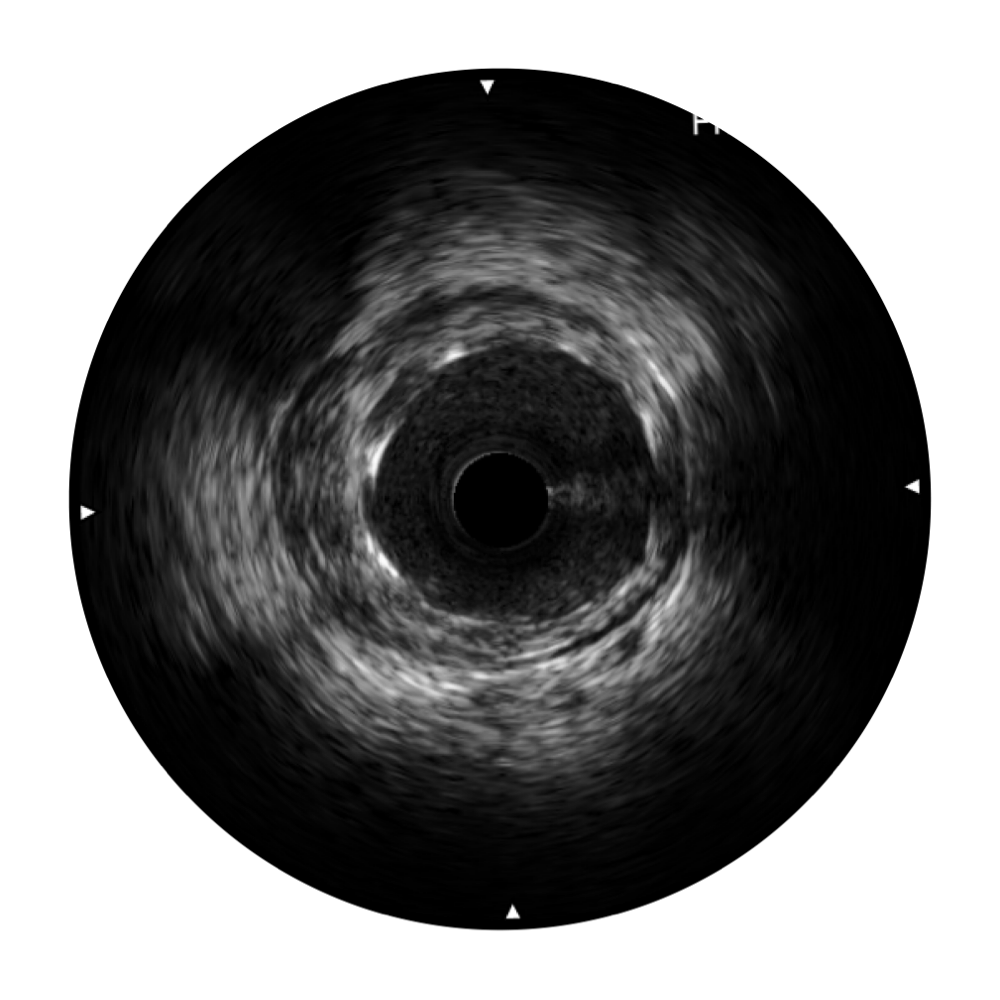

银河优越会宽频IVUS图像

传统IVUS图像

对比传统IVUS导管成像,银河优越会宽频IVUS图像的近场支架梁显影更细腻,远场中膜外血管仍清晰可辨,兼顾远中近,兼顾分辨力与穿透深度